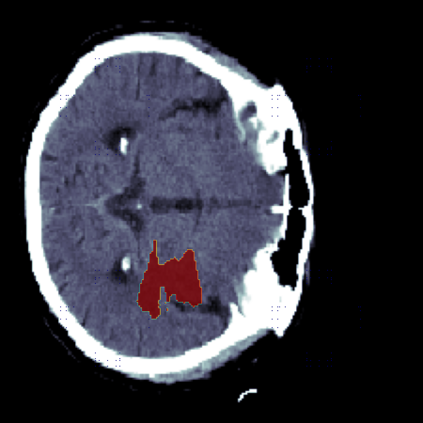

The sigmoid activation is the standard output activation function in binary classification and segmentation with neural networks. Still, there exist a variety of other potential output activation functions, which may lead to improved results in medical image segmentation. In this work, we consider how the asymptotic behavior of different output activation and loss functions affects the prediction probabilities and the corresponding segmentation errors. For cross entropy, we show that a faster rate of change of the activation function correlates with better predictions, while a slower rate of change can improve the calibration of probabilities. For dice loss, we found that the arctangent activation function is superior to the sigmoid function. Furthermore, we provide a test space for arbitrary output activation functions in the area of medical image segmentation. We tested seven activation functions in combination with three loss functions on four different medical image segmentation tasks to provide a classification of which function is best suited in this application scenario.